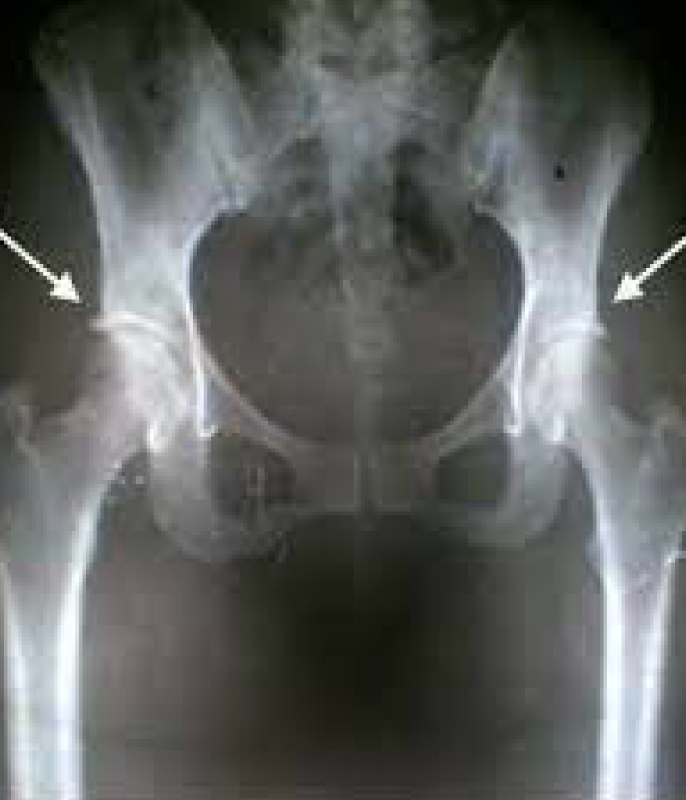

Es una patología común en el adulto joven deportista que cada vez está tomando más relevancia y que se caracteriza por una inadecuada relación femoroacetabular, con una clínica dolorosa e incapacitante de larga evolución, que puede simular otras patologías de la cadera, motivo por el cual, se debe realizar una anamnesis y una exhaustiva exploración física que nos oriente hacia esta patología, confirmando la sospecha diagnóstica mediante pruebas complementarias como la radiografía de pelvis y la resonancia magnética (RM). El tratamiento, en general, es quirúrgico. Debemos realizar un diagnóstico temprano ya que es una causa de artrosis precoz en el adulto joven.